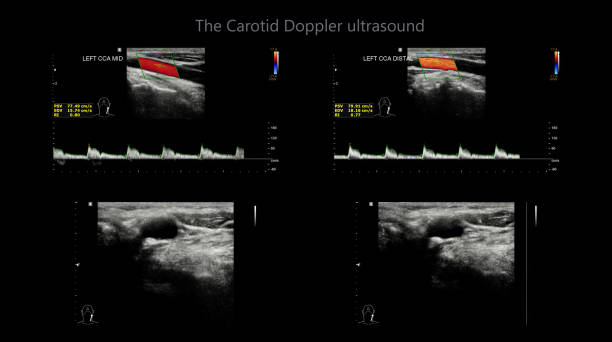

경동맥 초음파 검사의 원리

경동맥 초음파 검사는 초음파 기계를 사용하여 경동맥의 상태를 확인하는 검사입니다. 이 검사는 무해하고 비침습적이며, 빠르게 수행할 수 있어 환자에게 불편함을 주지 않습니다. 검사 과정은 다음과 같습니다.

- 환자는 안정된 자세로 앉거나 누워서 검사를 받습니다.

- 의사나 초음파 기술자는 초음파 젤을 사용하여 목 부위에 초음파 프로브를 적용합니다.

- 초음파 프로브는 고주파 소리파장을 방출하여 경동맥의 이미지를 생성합니다.

- 이미지를 컴퓨터 모니터에 표시하여 의사가 경동맥의 상태를 시각적으로 확인할 수 있습니다.

경동맥 초음파 검사로 알수있는병 - 검사 결과 해석

검사 결과를 해석할 때, 의사는 다음 사항을 고려합니다.

- 경동맥의 크기와 형태: 경동맥이 충분히 넓고 매끄럽게 유지되는지 확인합니다.

- 혈류 속도: 혈액이 경동맥을 흐르는 속도를 측정하여 혈액순환에 이상이 없는지 확인합니다.

- 혈액 응고물질의 존재: 콜레스테롤과 혈액 응고물질이 경동맥 벽에 쌓여 있는지 확인합니다.